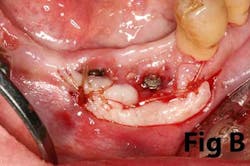

Surgical reconstruction of a deficient ridge/site begins with bone augmentation (i.e., lateral ridge graft, sinus augmentation, etc.), closely followed by soft-tissue augmentation (i.e., onlay graft, pedicle graft, etc.) When either cannot produce adequate ridge form for esthetics, prosthetic solutions are used to compensate for this deficiency. Soft-tissue augmentation, particularly those procedures to increase AG, is often overlooked.

Case No. 1

Case No. 2